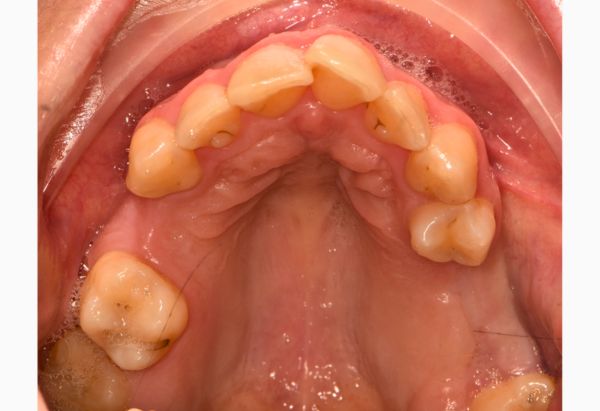

After

Stabilisation Treatment